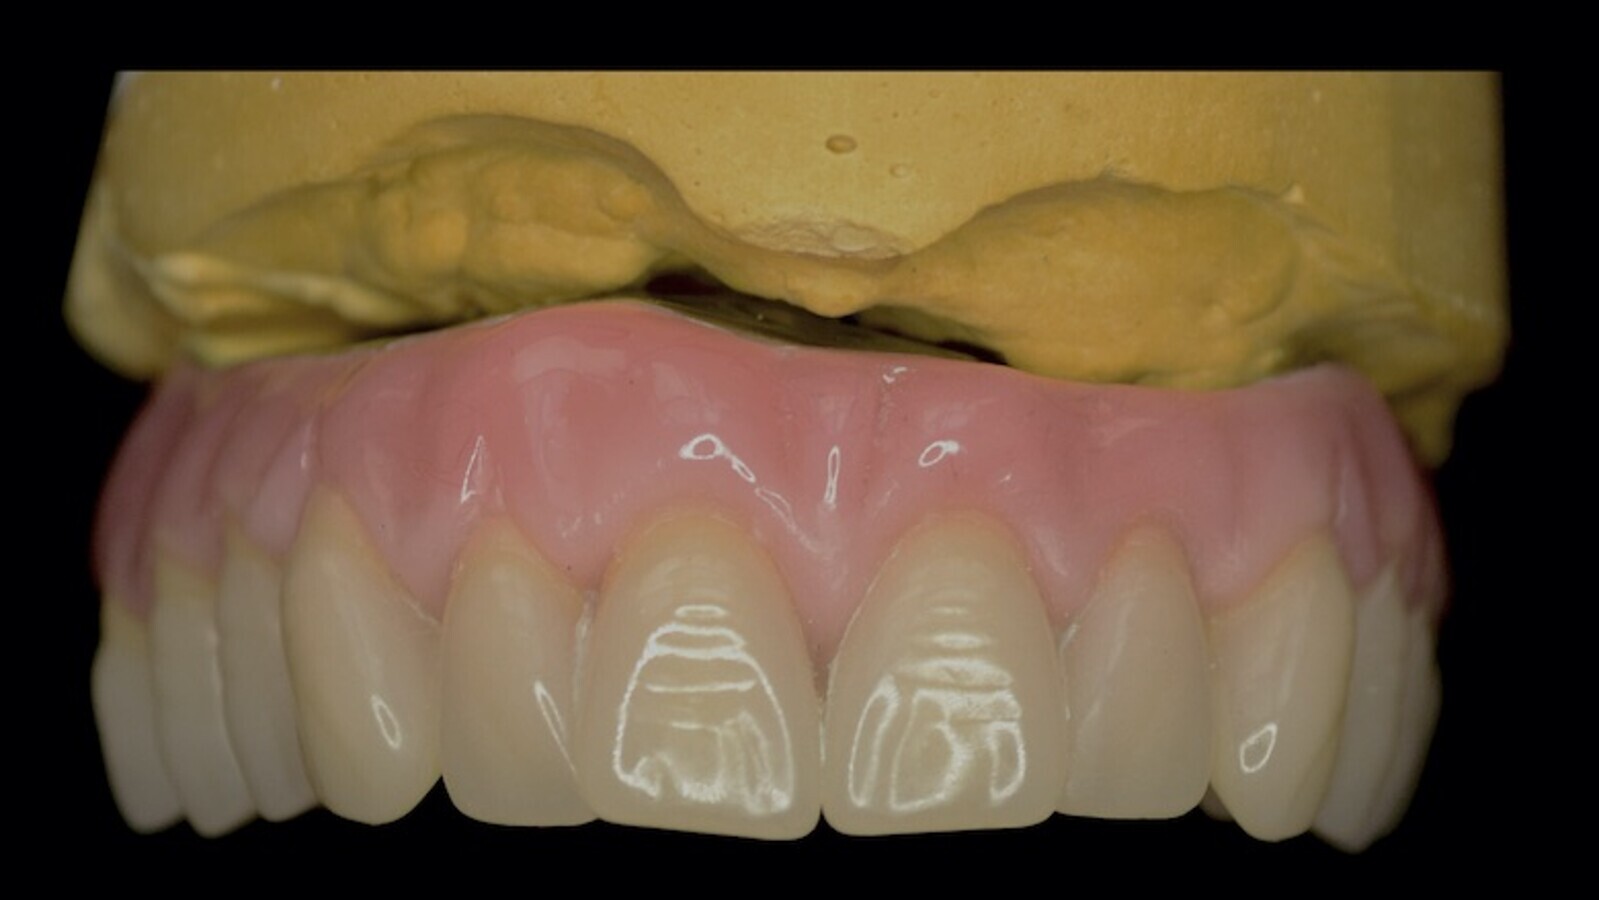

Restauración con implantes finalizada.

La implantología volvió a los pacientes más ambiciosos y demandantes de importantes rehabilitaciones, y con justa razón. Hoy en día, prácticamente no hay límites ni etarios ni resortivos-resectivos en los cuales no pueda lograrse la mayor de las rehabilitaciones, el mayor gold estándar, al que los pacientes pueden aspirar: me refiero, ni más ni menos, que a reconstituir su arco dentario completo fijo. Incluso con la posibilidad de remoción y mantenimiento que un simple mortal no implantado no tiene.